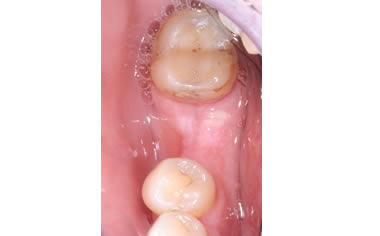

More back teeth replaced by dental implants

Case Five (4 images)